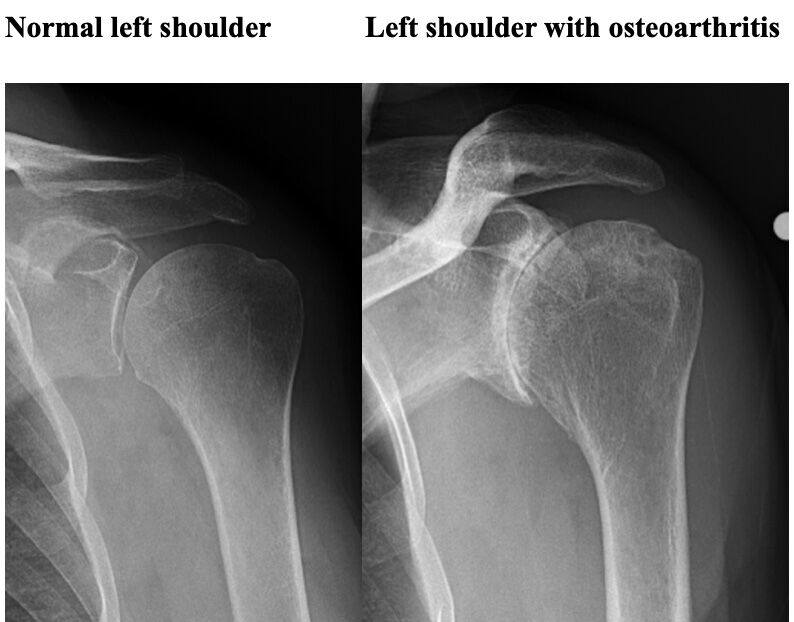

錯誤(B) 嚴重的關節炎(osteoarthritis)

嚴重OA無論在那個關節,都可明顯看到關節間隙縮小或消失

圖片來源:https://radiopaedia.org/cases/adhesive-capsulitis-frozen-shoulder-3、https://bmjopenquality.bmj.com/content/9/1/e000550、https://shoulderelbow.org/2016/11/21/calcific-tendinitis-calcifying-tendonitis/、https://universityorthopedics.com/what_hurts/shoulder_arthritis.html